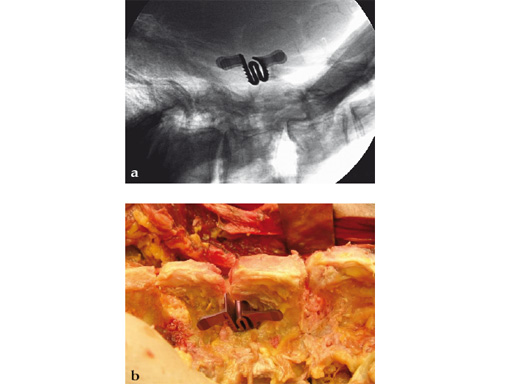

Fig 2ab A 66-year-old man with L3/L4, implant size 10.

Fig 1 X-ray shows dynamic extension 3 months postoperatively.

Fig 2 Intraoperative view with original stenofix implant in place.

A 66-year-old man with L3/L4, implant size 10.